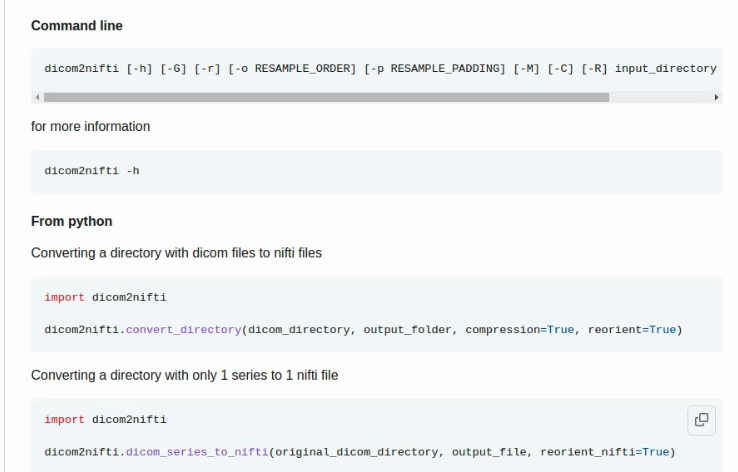

- dicom2nifti: 看起来很有前途:可使用命令行,也可以在python中调用 dicom2nifti 下载链接。